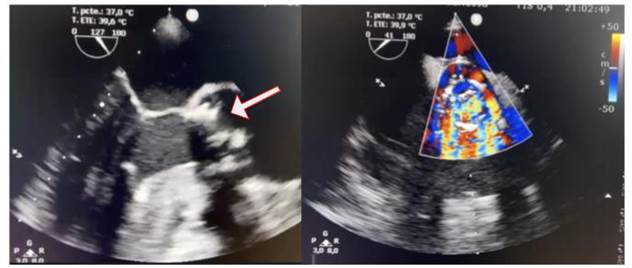

Se realiza un ecocardiograma transtorácico Doppler color, en el que se observa hipertrofia excéntrica del ventrículo izquierdo, función sistólica conservada, bioprótesis en posición aórtica estable, se registra una insuficiencia central con un tiempo de hemipresión (PHT) de 150 ms. Se produce un engrosamiento valvular con imagen móvil adherida a esta, con aumento de los gradientes 78/38 mmHg. Posteriormente, se realiza un ecocardiograma transesofágico Doppler color (Figura 3), que evidenció prótesis biológica en posición aórtica disfuncionante, con múltiples vegetaciones adheridas, la más grande de 8 mm por 5 mm, lo que genera destrucción del aparato valvular e insuficiencia severa (PHT 150 ms).

Figura 3 Ecocardiograma basal A. Transesofágico a 120 grados, se observan múltiples vegetaciones adheridas a bioprótesis aórtica, la más grande 8 mm por 5 mm (flecha). B. Doppler color a 45 grados, se observa jet de insuficiencia aórtica severa.